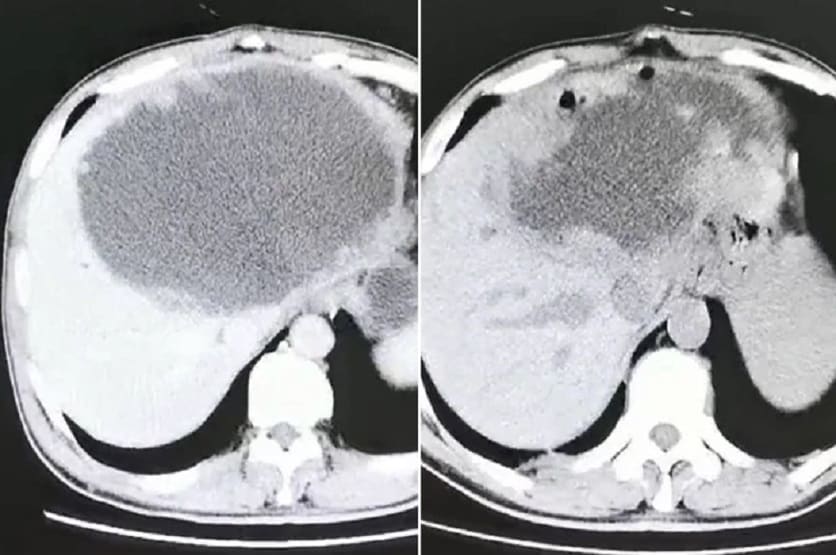

जब इस बीमारी को डॉक्टर दवाओं के द्वारा नहीं ठीक कर पाए, तो उन्होंने व्यक्ति का स्कैन किया. इस स्कैन में जो दिखा, वो देखकर डॉक्टर्स भी चौंक गए. शख्स को क्लोनोरकायसिस नामक एक इंफेक्शन हुआ था, जिसका कारण पैरासाइट (एक प्रकार की इल्ली) होता है, जिसे फ्लैटवॉर्म कहते हैं.

ये पैरासाइट वॉर्म उसके अंदर चला गया और फिर इस पैरासिटिक वॉर्म ने इस शख्स के लीवर में अंडे देने शुरू कर दिए. और यही धीरे-धीरे लीवर की बाईं ओर एक मवाद से भरी थैली का कारण बन गया. साथ ही डॉक्टरों को कई ट्यूमर भी मिले जो इस थैली के बाहर बढ़ने लगे थे.

रिपोर्ट के मुताबिक डॉक्टरों ने बताया कि प्रभावित हिस्सा 19 सेन्टीमीटर लंबा, 18 सेन्टीमीटर चौड़ा और 12 सेन्टीमीटर गहरा था. इस समस्या के साथ ही मवाद के कारण लीवर की दीवारों पर छोटे-छोटे ट्यूमर उभरने लगे थे.

अंत में डॉक्टरों ने ऑपरेशन के जरिए युवक के लीवर में भरा हुआ मवाद निकाला. कुछ समय बाद दोबारा स्कैन करने पर सूजन और ट्यूमर की शिकायत बनी रही तो युवक के लीवर को काटने का फैसला किया गया. शख्स के लीवर के डेड टिशूज में अनगिनत छोटे-छोटे अंडे पाए गए थे.